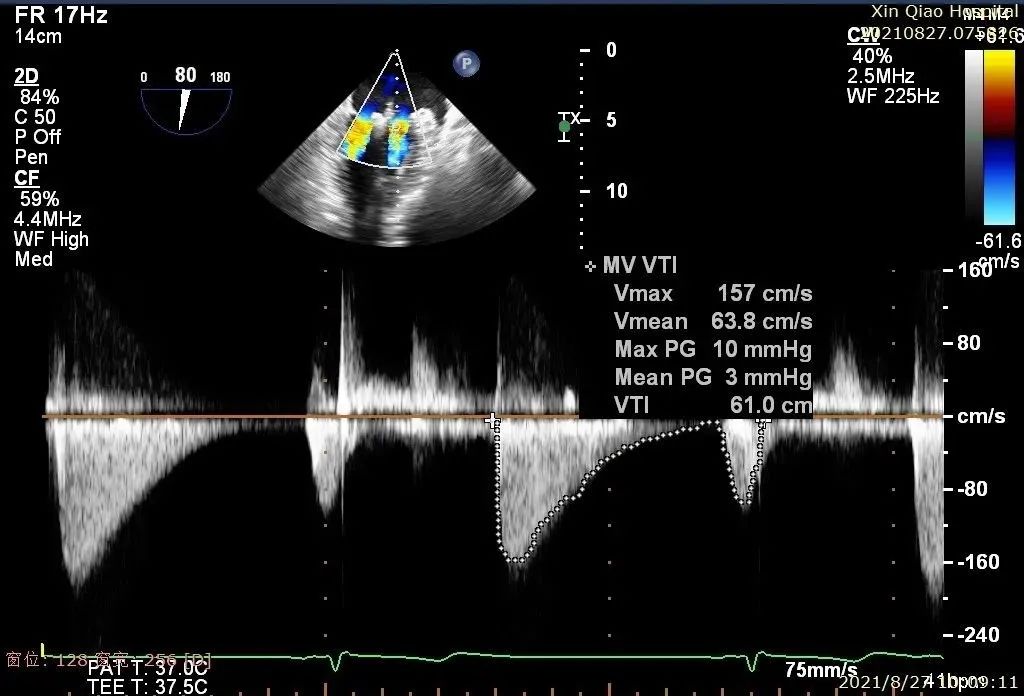

术中超声

在麻醉和体外循环团队保驾护航下,器械经股静脉穿刺房间隔,通过输送系统送入患者左心房,到达二尖瓣膜反流处,在经食道超声及DSA引导下,术者通过反复评估二尖瓣膜脱垂范围、抓捕位置、反流程度,精准夹合,成功植入两枚DragonFly瓣膜夹。

术后即刻,患者反流显著减小,二尖瓣反流从4+减少到1+以下,左房压下降,血流动力学改善明显,手术取得了圆满成功。